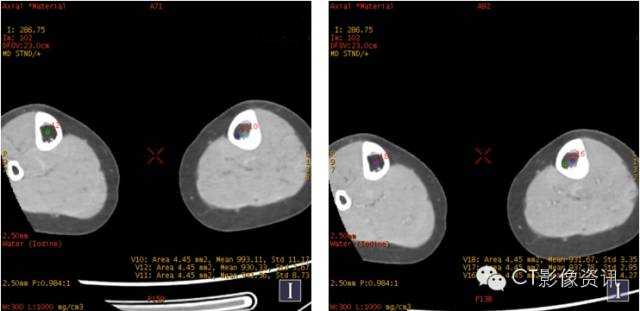

碘基与单能量融合伪彩图,对显示病变比较敏感。